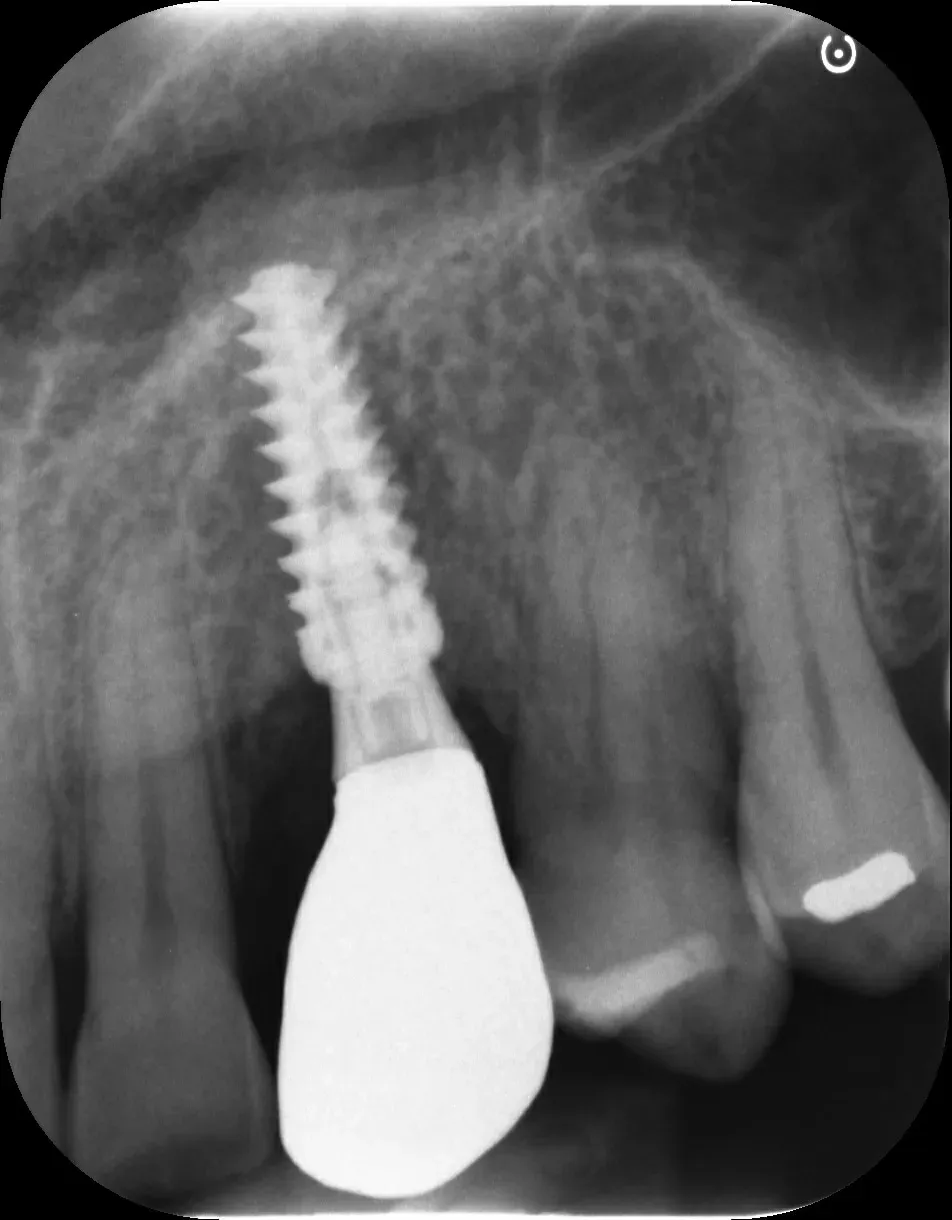

Il tissue level posizionato male

Gli impianti tissue level nascono con un obiettivo preciso: spostare l’interfaccia protesica lontano dall’osso, a livello dei tessuti molli. Il microgap — quella zona di colonizzazione batterica inevitabile tra impianto e componente protesica, caratteristico soprattutto di alcuni tipi di connessione — viene così allontanato dalla cresta ossea.

Utilizzarli come se fossero bone level, o peggio ancora affondarli più in profondità, è un errore biologico grave (ne ho parlato anche in questo articolo sulle conseguenze biomeccaniche del malposizionamento). Quando il microgap si trova troppo vicino alla cresta, si innesca un riassorbimento osseo progressivo. Di fatto, in tali casi, parliamo di una vera e propria invasione dello “spazio biologico”, concetto prezioso in odontoiatria. La peri-implantite, in questi casi, non è un rischio: è una conseguenza prevedibile ed è dietro l’angolo .

Gli impianti transmucosi devono essere posizionati transmucosi, soprattutto se hanno connessioni non particolarmente “sigillanti”. Usati in tal guisa, sono perfetti. Le immagini che seguono dimostrano che i transmucosi, se posizionati al giusto livello verticale, causano ZERO riassorbimento della cresta ossea.

Non sono fatti per invadere lo spazio biologico. Devono starne fuori.